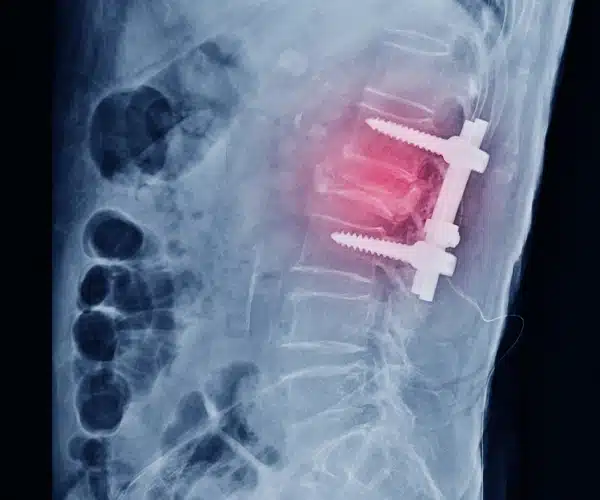

Qué es una artrodesis vertebral

La artrodesis o fusión vertebral es la técnica más usada para el tratamiento de los problemas de espalda, consiste en fijar mediante tornillos e injerto dos vértebras para que estas no se muevan. Para ampliar el éxito de una artrodesis vertebral en muchas ocasiones además de los tornillos pondremos una caja entre los cuerpos vertebrales para aumentar el porcentaje en el que conseguimos la fusión vertebral.

radiografia artrodesis vertebral

Cuando se realiza una artrodesis vertebral

Se realiza una fusión vertebral en los casos de discopatia severa, en los casos de espondilolistesis con inestabilidad o cuando preveamos que para liberar las estructuras nerviosas hay que retirar mucho hueso y podamos dejar la vértebra inestable. Es en estos casos cuando necesitamos realizar una fijación.

Una vez que hemos introducido la caja intersomática procederemos a poner los tornillos pediculares de forma percutánea.